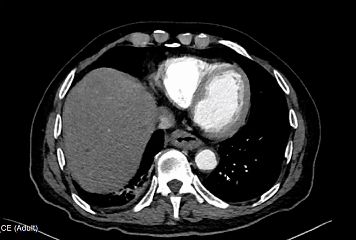

会诊的血管外科潘以锋医生看到患者的增强 CT 结果提示:右侧腰大肌明显肿胀、密度不均,大量脓肿;右肾周围伴有渗出、右侧髂总动脉瘤、瘤体周围形态不规整,可见造影剂外溢。

图源:治疗团队提供

这些表现提示着患者符合「感染性髂总动脉破裂」的诊断,此外患者同时也存在着腰大肌脓肿,肾周脓肿,腹腔出血和腹腔感染等情况。

通俗来讲,就是患者右下腹的一根大动脉鼓了一个「大包」,形成了动脉瘤,而这个动脉瘤经过紧邻的腰部脓肿长时间地侵蚀,本就脆弱的动脉壁被泡烂了,血液直接漏在了患者肚子里。